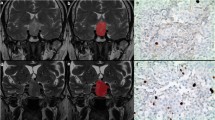

Two hundred forty-six pituitary adenoma patients (84 aggressive, 162 non-aggressive) who underwent preoperative MRI were retrospectively reviewed. The patients were divided into training (n = 193) and testing (n = 53) sets. Clinical information, shape-related, and textural features extracted from the tumor volume on contrast-enhanced T1-weighted images (CE-T1WI), were compared between aggressive and non-aggressive groups. Variables with significant differences were enrolled into Pearson’s correlation analysis to weaken multicollinearity. Logistic regression models based on the selected features were constructed to predict tumor aggressiveness under fivefold cross-validation.

Sixty-five imaging features, including five shape-related and sixty textural features, were extracted from volumetric CE-T1WI. Forty-seven features were significantly different between aggressive and non-aggressive groups (all p values < 0.05). After feature selection, four features (SHAPE_Sphericity, SHAPE_Compacity, DISCRETIZED_Q3, and DISCRETIZED_Kurtosis) were put into logistic regression analysis. Based on the combination of these features and Knosp grade, the model yielded an area under the curve value of 0.935, with a sensitivity of 94.4% and a specificity of 82.9%, to discriminate between aggressive and non-aggressive pituitary adenomas in the testing set.

The radiomic model based on tumor shape and textural features study from CE-T1WI might potentially assist in the preoperative aggressiveness diagnosis of pituitary adenomas.